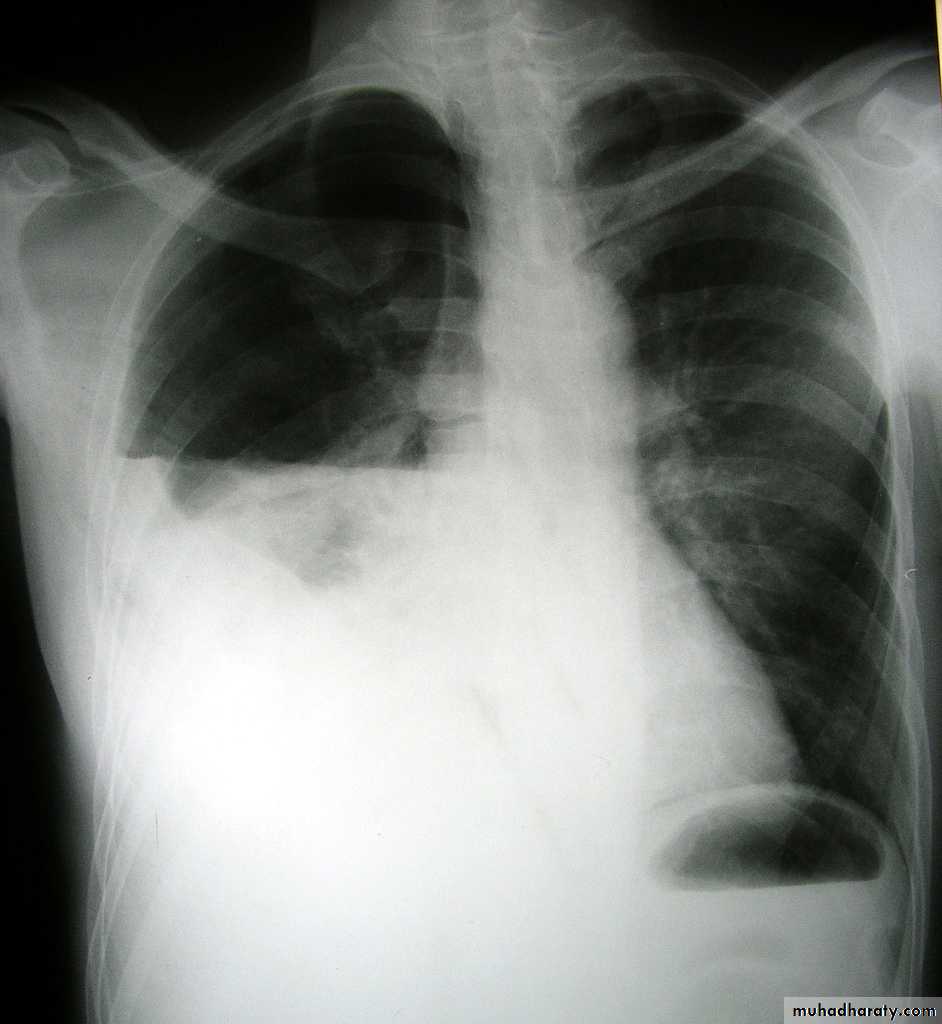

X-ray of pleural effusion

Massive right effusion